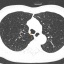

Tin mới y tế ngày 14/3: Phát hiện ung thư não từ dấu hiệu bị choángHai năm nay, bà Liên (60 tuổi) thường xuyên bị choáng váng nhẹ nhưng cho rằng do mệt mỏi nên không đi khám. Chỉ đến khi thực hiện kiểm tra sức khỏe chuyên sâu theo lời khuyên của con trai, bà mới phát hiện trong não có nhiều khối u, nghi ngờ di căn từ phổi. -